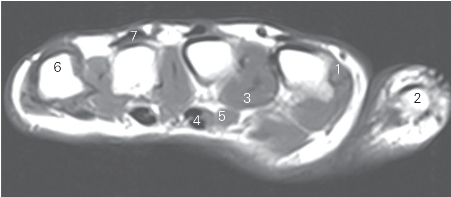

图4-48 经掌骨远侧四分之一的横断层MR T1加权图像

1 骨间背侧肌 dorsal interossei 2 拇指近节指骨 proximal phalanx of thumb

3 骨间掌侧肌 palmar interossei 4 屈肌腱 tendon of flexor

5 蚓状肌 lumbricales 6 第五掌骨 5th metacarpal bone

7 伸肌腱 tendon of extensor